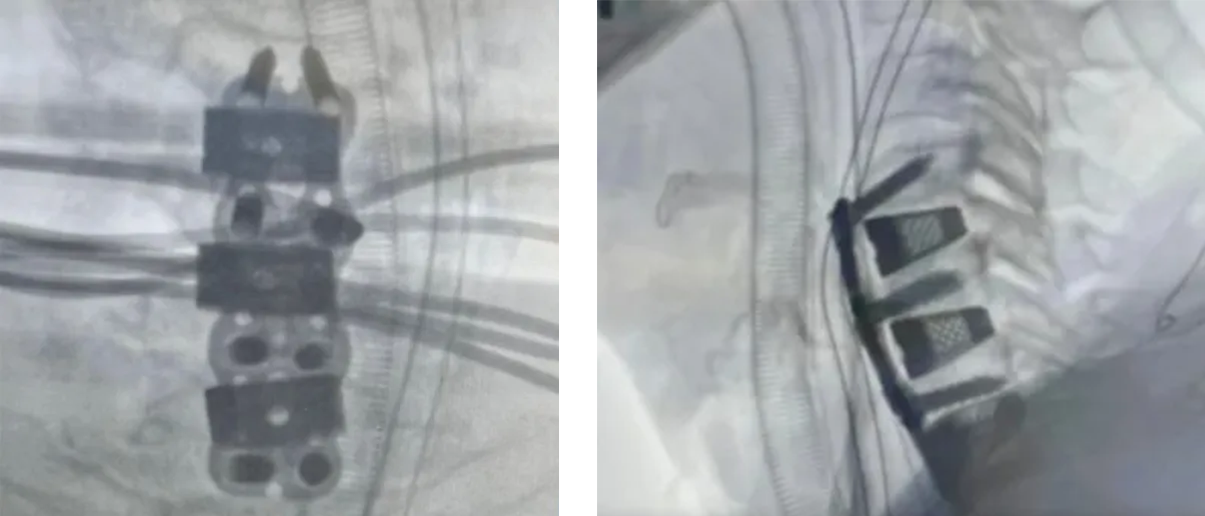

Dr. Fernando Villamil recently performed a three-level anterior cervical discectomy and fusion (ACDF) at Ashford Hospital in Puerto Rico using ZSFab’s 20° InterConnect™ hyperlordotic cervical cages. This case represents the first clinical use of our 20° hyperlordotic implant design, which incorporates advanced 3D-printed Triply Periodic Minimal Surface (TPMS) lattice architecture and nano-surface technology. The procedure achieved an impressive total of 60° of lordosis correction.

This milestone highlights the precision and clinical effectiveness of ZSFab’s implants in restoring optimal cervical alignment. Additionally, a recent study, presented at the Orthopaedic Research Society (ORS) Annual Meeting in 2023, showcases ZSFab cervical cages’ exceptional subsidence performance. Compared to leading competitors with annular and truss designed cages, ZSFab’s cage demonstrates a significant (+14%) improvement in subsidence resistance, even against larger-footprint devices, highlighting the efficacy of our product in addressing subsidence. With 107 cervical interbody sizes available, ZSFab’s comprehensive portfolio enables patient-specific solutions that support meaningful, durable deformity correction and helps optimize long-term clinical outcomes.